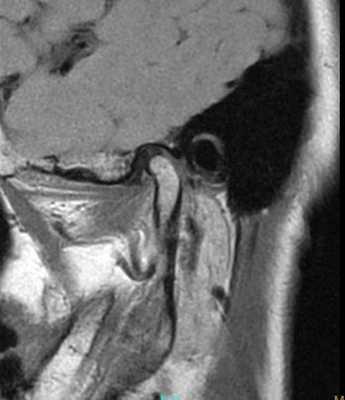

69-летняя пациентка с основными жалобами на боли в проекции челюсти, ограниченное открытие полости рта и невозможностью выдвинуть челюсть вперед обратилась за стоматологической помощью. Со слов пациентки ее симптомы начали развиваться около 6 месяцев назад: именно тогда она заметила, что ей трудно выдвигать челюсть вперед, чтобы посвистеть к своей собаки. По данным анамнеза на протяжении около 50 лет больная отмечала «выскакивание» и «пощелкивание» челюсти с левой стороны, и данные симптомы прекратились приблизительно в то время, когда ей стало трудно выдвигать нижнюю челюсть вперед. В ходе клинического осмотра было обнаружено, что максимальная величина межрезцового расстояния составляла 35 мм, при этом в ходе максимального открытия полости рта челюсть несколько смещалась влево. После массажа и растяжения левой жевательной мышцы и сустава снизилась интенсивность болевых ощущений, однако объем движений не увеличился. Таким образом был поставлен диагноз левостороннего смещения суставного диска без сопровождающейся редукции ВНЧС. Пациентка была направлена на магнитно-резонансную томографию (МРТ), и для исследования локализации и состояния диска при открытом и закрытом рте. Данные МРТ позволили установить, что с левой стороны отмечалось переднее смещение суставного диска в обеих положения, что также подтверждает диагноз смещения без редукции (фото 1-4).

Фото 1. МРТ-скан правого ВНЧС при закрытом состоянии рта: визуализация положения диска.

Фото 2. МРТ-скан правого ВНЧС при открытом состоянии рта: визуализация положения диска.